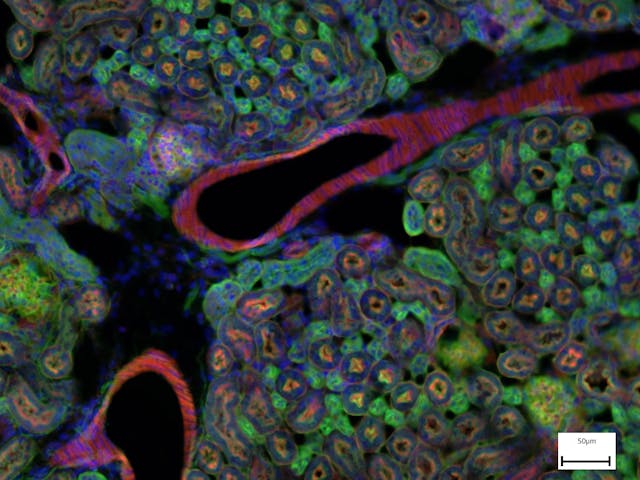

印度麂,成纖維細胞 小鼠腎臟熒光圖像

小鼠腎臟熒光圖像 Novicula Lyra